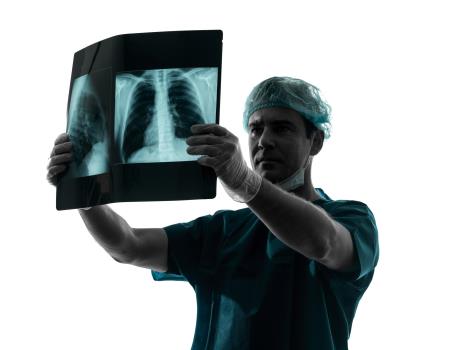

Koliko je uspešno lečenje?

- Kada se bolest pojavi, uspešnost lečenja zavisiće na prvom mestu od stadijuma bolesti u trenutku postavljanja dijagnoze. Učestalost komplikacija i smrtnog ishoda posle operacija pluća znatno je smanjena u poslednjih 20 godina.

rak-pluca.jpg

Foto: Profimedija